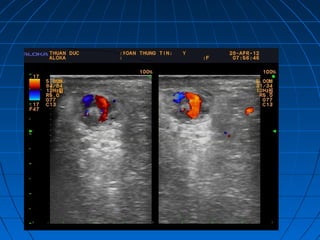

 Tiêu chuẩn hình thái học: môn vị phìTiêu chuẩn hình thái học: môn vị phì

đại nằm kéo dài , hình cocard trênđại nằm kéo dài , hình cocard trên

nhát cắt ngang, tăng sinh mạch máunhát cắt ngang, tăng sinh mạch máu

trong cơtrong cơ

(tăng sinh mạch máu)(tăng sinh mạch máu)